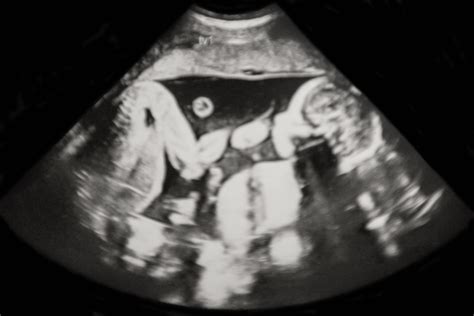

A hármas vagy többes ikrek lehetnek egypetéjűek, kétpetéjűek vagy ezek kombinációi is. Leggyakrabban az első ultrahangvizsgálat során derül ki, általában a 6-9. hét között. Ilyenkor az orvos nemcsak a terhesség meglétét igazolja, hanem a szívhangokat is ellenőrzi - és ha kettőt hall, az egyértelmű jele az ikerterhességnek. Az ultrahangon jól látszanak a különálló embriók, valamint az is, hogy van-e közös vagy külön méhlepényük és magzatburok-rendszerük, ami segít eldönteni, hogy egypetéjű vagy kétpetéjű ikrekről van-e szó.